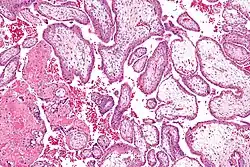

Vilosidades coriónicas

Vilosidades coriónicas (português europeu) ou vilosidades coriônicas (português brasileiro) são vilosidades que florescem na placenta a partir dos córios de forma a permitir o máximo de área de contacto com o sangue materno durante uma gravidez.[1]